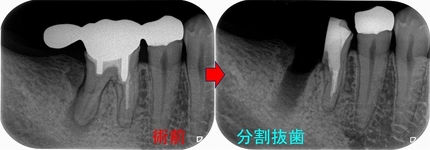

患者さんと話し合い、近心根はヘミセクションをして残す 遠心根は抜歯

この後遠心根抜歯

2026 EEdental FUD (4).jpg

口腔外科で移植をしてもらい、移植歯の根管治療を行い

ある程度咬めるように治させてもらいました。

10年経過して、そこまで悪い感じはありません。

患者さんにも「先生にそんなに持たないかもしれないよと言われていましたが10年持っています。意外と持つものですね!」と言われましたが、

ホント最初の延長ブリッジの方がかなり良い条件でしたが、折れてしまった。

パフォレーション+分割抜歯、移植した歯という条件の悪いケースで10年経過している。。。